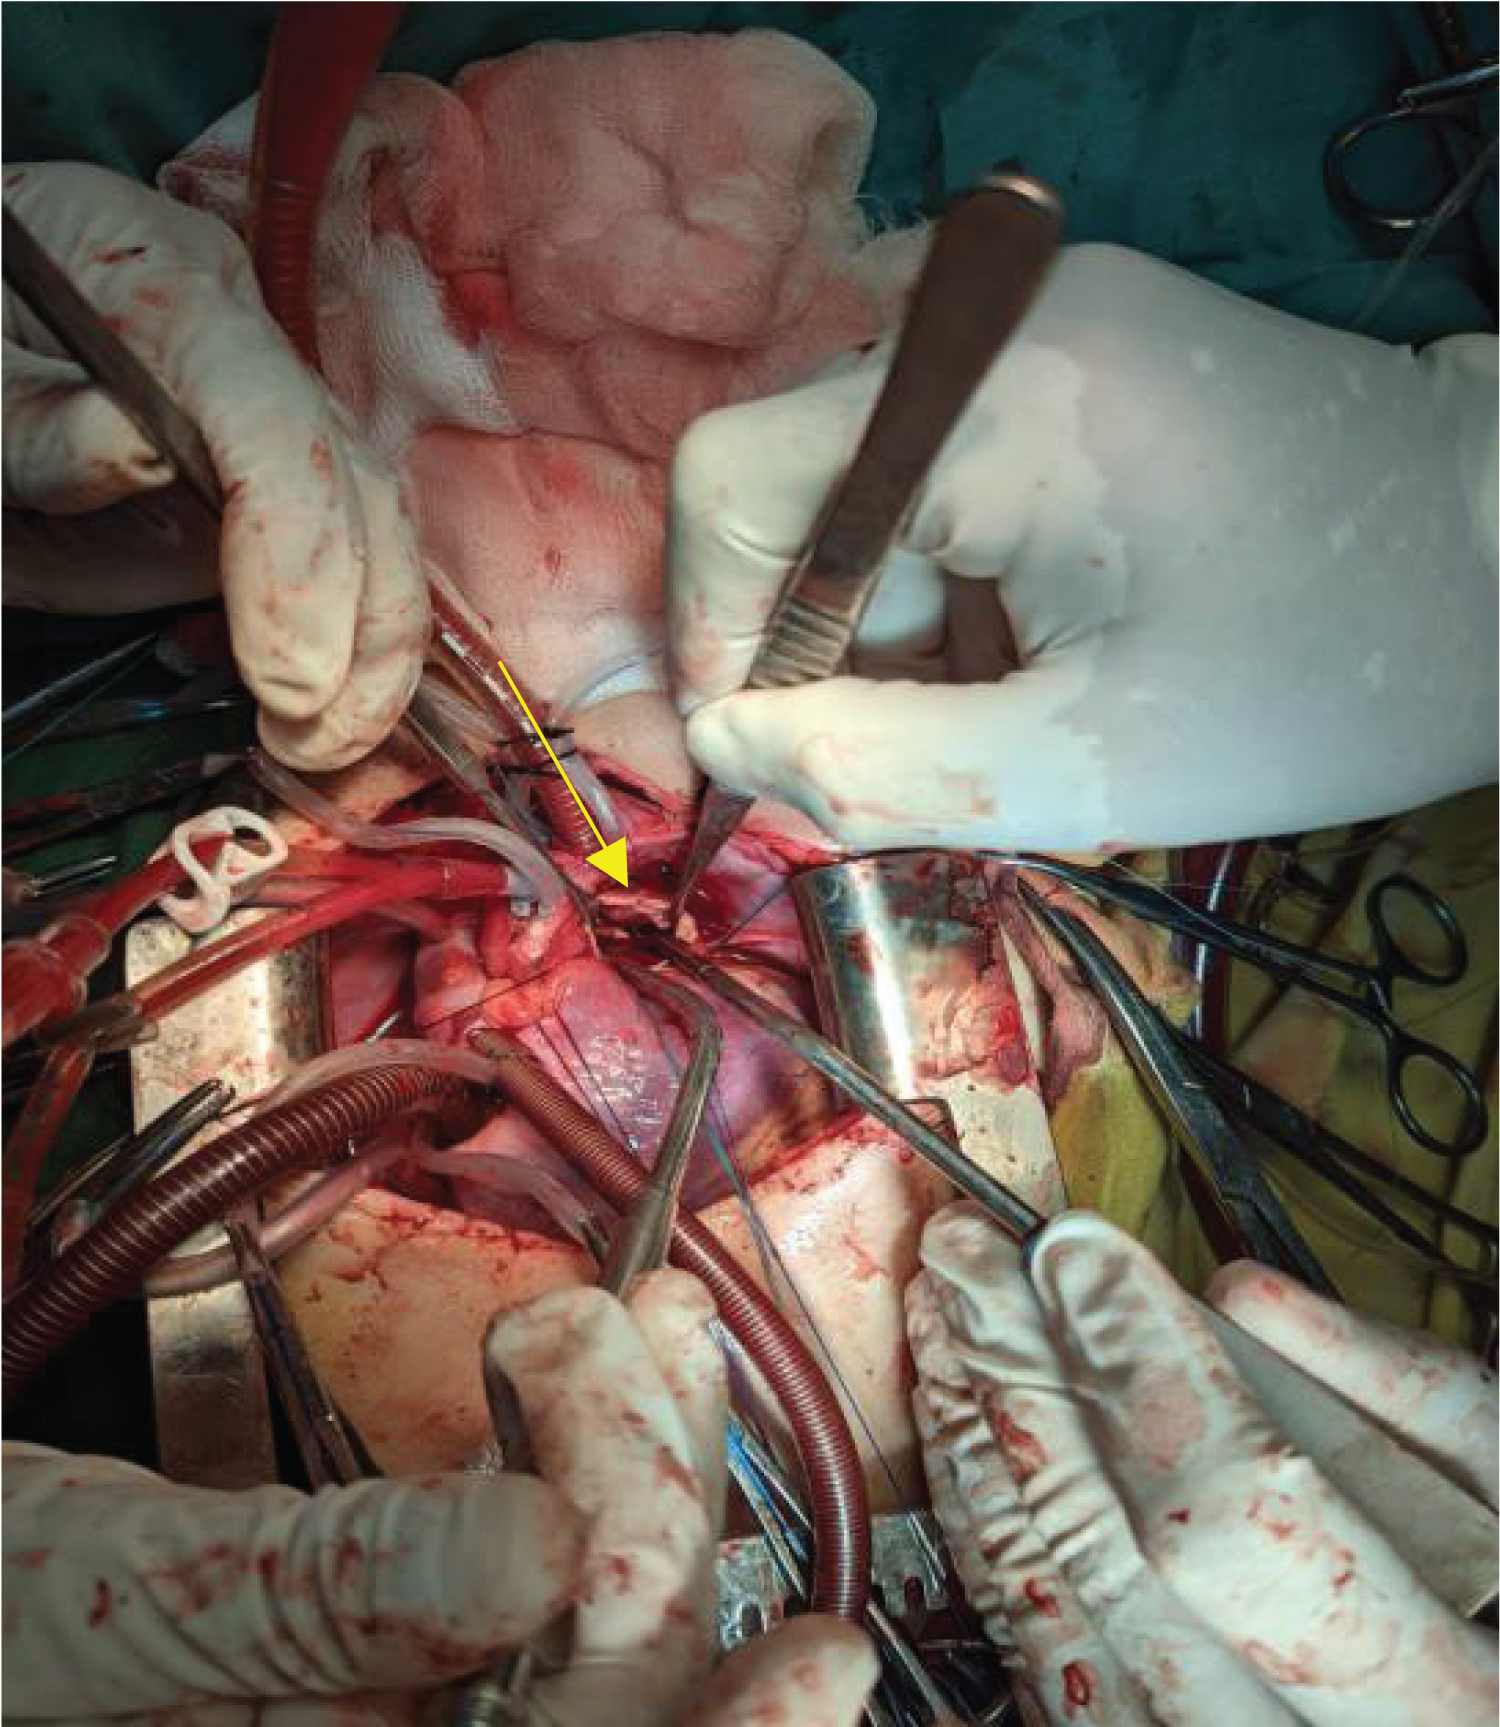

Regarding the length and size of the patent ductus arteriosus, the patient was in need of surgical intervention. Depending on the age of the patient and the size of the PDA, a median sternotomy was performed. After opening the chest wall, the heart contractility was good, with a normal average size. Searching for PDA took about 30 minutes; it was deep, short, and large (12-14 mm). Then we measured the direct pressure from the aorta and pulmonary artery, which revealed the similarity of pressure and indicated the possibility of irreversibility. More than 30 minutes were given to discussion with the pediatric cardiologist for the best next step and with the patient's family. Eventually, direct closure through the pulmonary artery by using a pericardial patch was the final decision to make for this young girl. The heart was connected to the cardiopulmonary machine, but without using cardioplegia (off-pump), an incision was made through the pulmonary artery, and we started to implant the patch after identifying the site of the PDA. By using Proline 5-0, we stitch the pericardial patch to the PDA opening using the matrix method to give a chance for future residual shunting formation. Decannulation was done smoothly, with good local homeostasis and closure of the chest (Figure 1).

Figure 1: Intra-operative photo demonstrate the closed PDA and pericardial patch (the arrows). View Figure 1